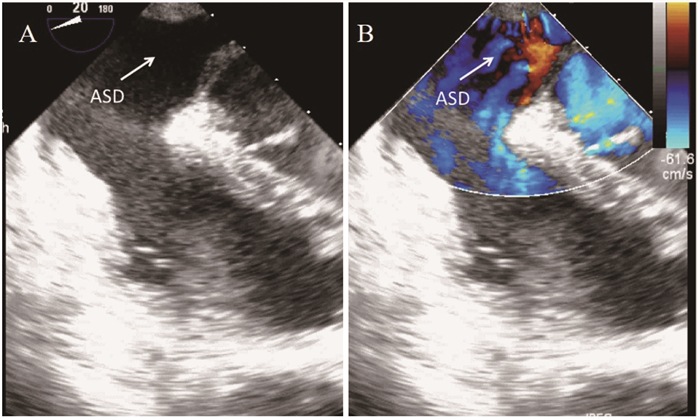

手术经过 患者入院完善检查后, 行人工房间隔再造术, 术中行经食管超声心动图(trans esophageal echocardiograhy, TEE)提示(

A:Transesophageal echocardiogram confirmed that the defect close to the ostium of the coronary sinus, which is a Type Ⅳ UCSS.B:Color Doppler showing left to right shunt.

图 2 无顶冠状静脉窦综合征(UCSS)患者经食道超声心动图(TEE)图像

Fig 2 Unroofed coronary sinus syndrome (UCSS) shown by transesophageal echocardiography (TEE)